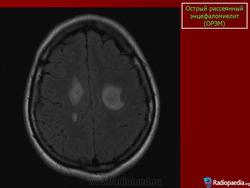

Основу патоморфологического процесса составляют периваскулярные множественные очаги демиелинизации с участием микроглии. Локализация процесса различна: белое вещество больших полушарий мозга, ствол мозга, спинной мозг. Периаксиальный демиелинизирующий процесс обнаруживается и в спинномозговых корешках и нервах конечностей.

Диагностика. Диагноз основывается на остром инфекционном начале, наличии симптомов мультифокального полисистемного поражения. Дифференцировать рассеянный энцефаломиелит следует от энцефаломиелитов при кори, ветряной оспе, краснухе. Основное значение при этом имеют данные анамнеза. Более сложен дифференциальный диагноз с рассеянным склерозом. В большинстве случаев окончательный диагноз устанавливается после длительного наблюдения. Наличие рецидивов и ремиссий свидетельствует о рассеянном склерозе.